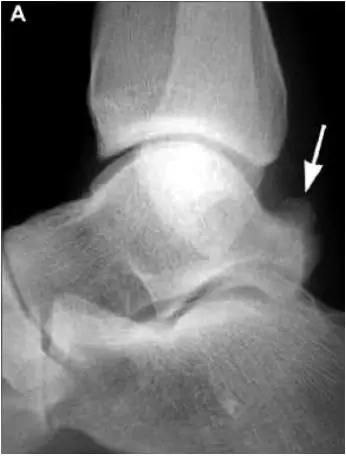

X线平片示胫骨后部骨赘形成,MR质子像黑箭示胫骨内后侧骨赘形成,白箭示内后侧软组织增厚, 白箭头:胫后肌腱;黑箭头:趾长屈肌腱